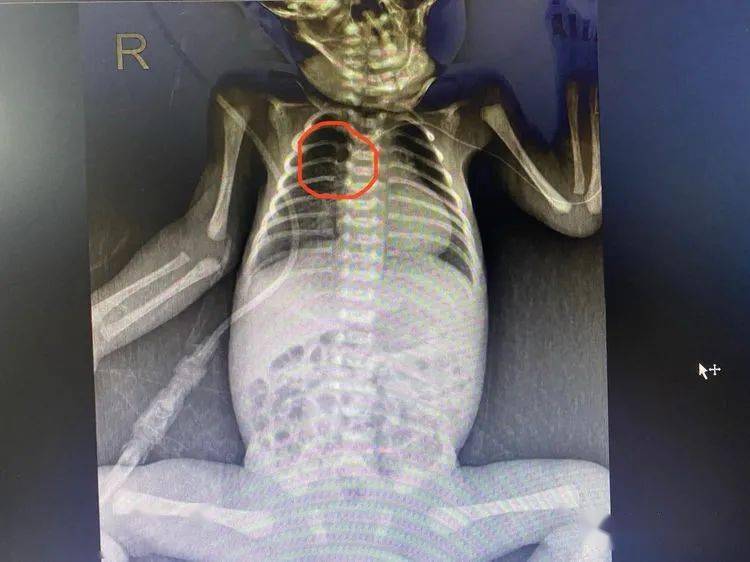

胸部x线进行picc导管定位,导管头端位于上腔静脉中下段截止发稿时picc